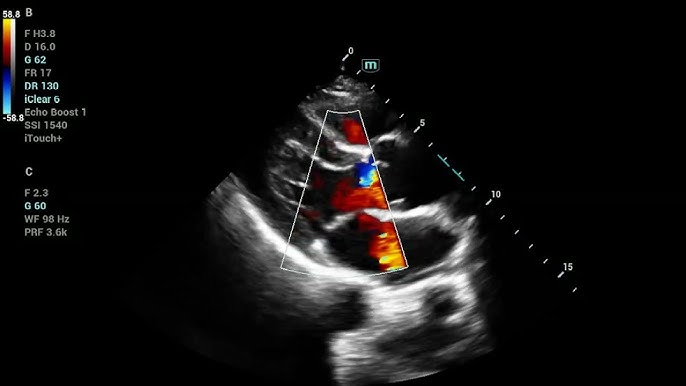

- Glazing Flow – three-dimensional color rendering

- CW Doppler – Continuous Wave Doppler